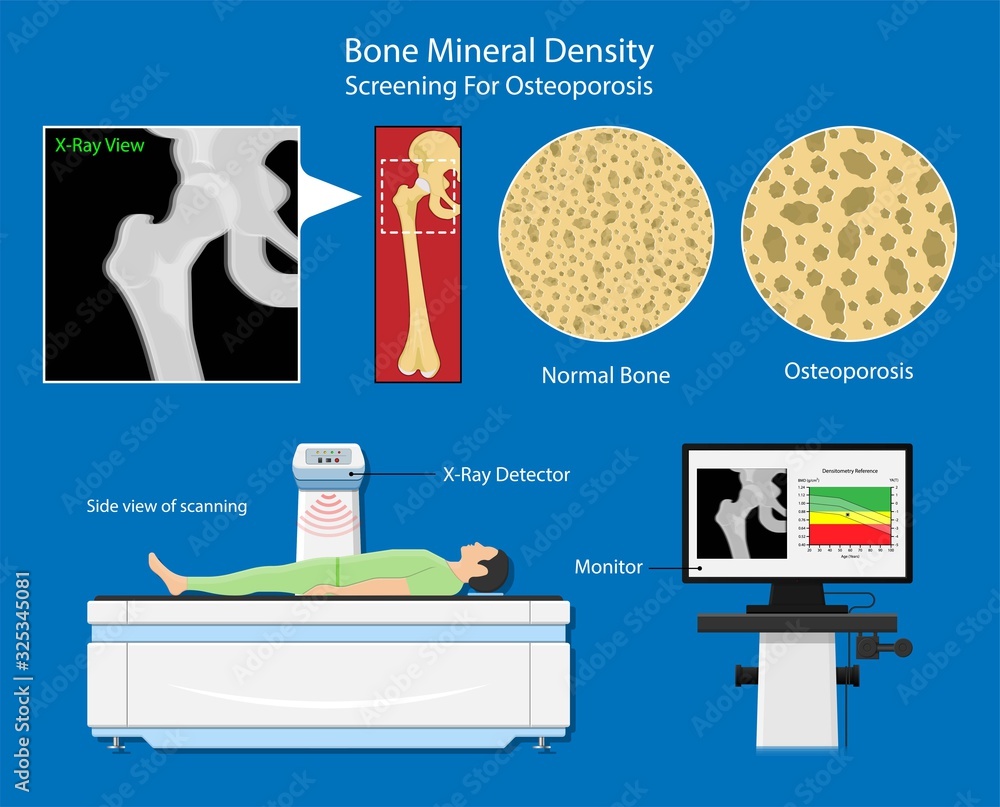

Osteoporosis The Bone School

How Osteoporosis And Bone Loss Can Be Reversed Naturally Osteoporosis

BMD Measurement Area In The Lumbar Spine And Femur A Femoral Neck

BMD Bone Mineral Densitometry

Bone Mineral Density BMD Osteoporosis Dual Energy X ray Absorptionmetry

Bone Mineral Density Radiology World